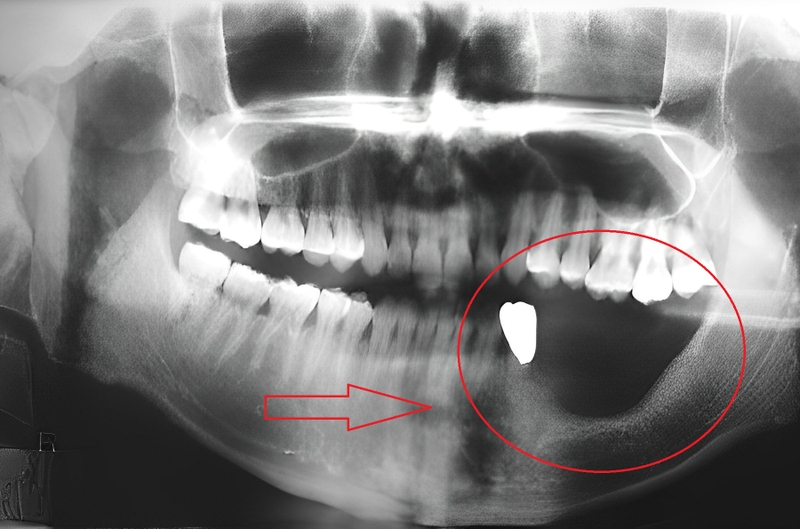

Bệnh hoại tử xương là tình trạng các tế bào mô xương chết dần cho nguồn cung cấp máu nuôi bị gián đoạn tạm thời hay vĩnh viễn. Đây được cho là nhóm bệnh hoại tử vô mạch hay hoại tử vô trùng. Hoại tử xương hàm là tình trạng hoại tử xương xảy ra ở xương hàm - xương di động duy nhất ở hộp sọ con người. Khi các tế bào mô xương hàm không được cung cấp máu nuôi đầy đủ sẽ yếu dần đi và dẫn đến hoại tử.

Một số bệnh nhân bị bệnh hoại tử xương hàm do sâu răng nhưng không được điều trị sớm. Sau một thời gian răng sâu, vi khuẩn xâm nhập vào tủy răng gây viêm tủy xương hàm dẫn đến các biến chứng nguy hiểm trong đó có hoại tử xương hàm.

Bệnh tiêu xương ổ răng hay còn gọi là bệnh tiêu xương hàm xảy ra khi chất lượng và mật độ xương hàm bị suy giảm khiến nướu bị teo, gương mặt biến dạng,… Tiêu xương hàm xảy ra chủ yếu do nguyên nhân viêm nha chu và mất răng. Khi mất răng, xương hàm có một khoảng trống ở chân răng nên không còn lực tác động lên xương hàm. Lâu dần sẽ dẫn đến việc tiêu xương. Khi bị viêm nha chu, nướu sẽ bị viêm và tụt gây hở chân răng. Khi đó, các dây chằng và xương bao bọc quanh răng bị tiêu hủy dần.